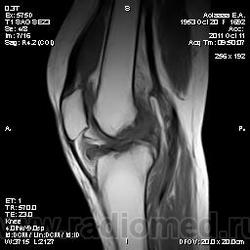

Дискуссия о природе "структры" в проекции передней поврехности метадиафиза бедренной кости.

Две версии: А. костно-хрящевой экзостоз. Б. разрастания сумки.

Я за экзостоз, но Вставьте снимки!))

МРТ изобрели зря.

Всё же не впечатляет масштаб.

Не очень понял. Мало картинок? Небольшой экзостоз? Неинтересный дифряд?

Они же не НЕ увеличиваются. Размер как на превьюшках: 256 x 256 тoчeк. Так и задумано?

Да, надо отметить, что "это" прекрасно видно на рентгенограммах. Вопрос к автору ветки - кто направил пациента на МРТ и с каким диагнозом?

Пациента на МРТ прислали с травмой. "Это" было выявлено в ряду другой патологии как случайная находка. Рентген не было возможности сделать - дистанционная диагностика. Хотя это конечно была первая мысль. Спасибо за внимание к посту.

Окончательное мнение - костно-хрящевой экзостоз. Прилагаю РКТ коленного сустава (пациент не тот, что на МРТ)

Валентин Львович, хочу обратить Ваше внимание, что это два разных кейса со сходной на мой взгляд патологией - костными экзостозами (другую временно опускаем) - взгляд со стороны МРТ и РКТ

За надколенником по передней поверхности бедренной кости на МРТ и РКТ (наверное не так наглядно) - костно-хрящевой экзостоз.

+ на РКТ проекционно на уровне средней трети диафиза бедренной кости кпереди от нее - фокусы хондроматоза.

tatyana, Вы в чем то правы. Складывается впечатление что кортикальная пластинка бедренной кости почти не изменена (или не изменена вовсе). Поэтому и были сомнения. Кроме того можно отметить, что вся синовиальная оболочка бурсы тотально утолщена, что тоже наводила на определенные соменения. Наверное изменение кортикальной пластинки, которые абсолютно четко увяжут заключение с костно-хрящевым экзостозом, можно указать с "натяжкой". Скорее это волевое решение в пользу костно-хрящевого экзостоза. Еще были мнения "вилонодулярном синовиите", а также "хондроматозе". Так что возможны варианты.